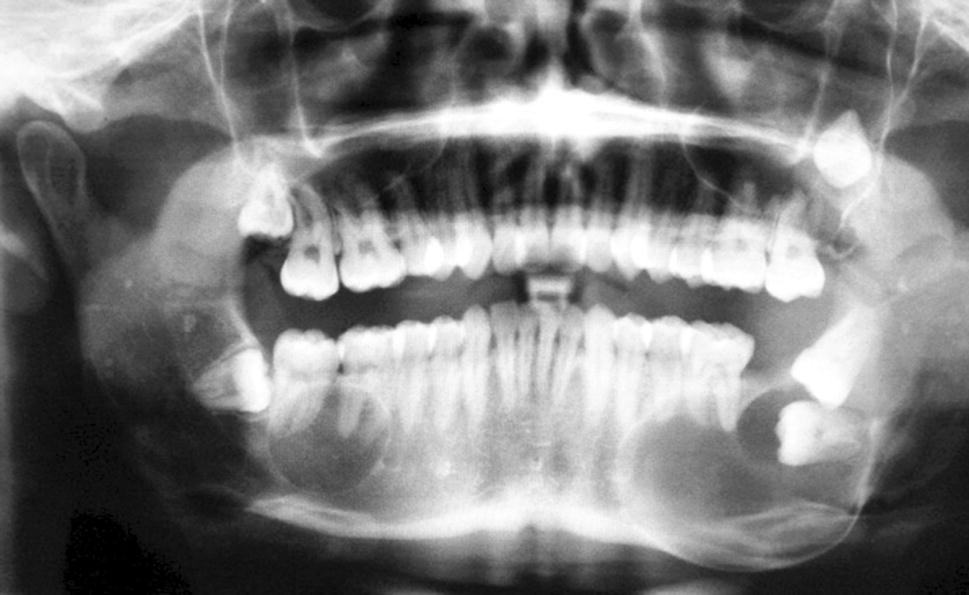

A 23-year-old male presented with three lesions, two in the mandible and one in the maxilla. An orthopantomogram (OPT) radiograph revealed three cystic lesions, the mandibular lesions were both well-defined and corticated (Fig. 1). In the right body of the mandible, a spherical radiolucency was noted overlying the roots of the lower right first and second molars. In the left body of the mandible, there was a larger radiolucent lesion with evidence of cortical expansion and displacement of the lower left second and third molars. A less well-defined radiolucency was seen in the left posterior maxilla. This lesion appeared to be multilocular and had inverted the third molar tooth and displaced it upwards into the posterior wall of the antrum.

Fig. 1

OPT from case 1 showing bilateral mandibular lesions and a cystic lesion associated with the displaced upper left 8 (UL8)

A review of OOCs showed that 93% of cases were unilocular [7] and this is reflected in the cases presented here, with only the lesions in the left maxilla and mandible of case 1 (Fig. 1) showing a multilocular appearance. The cases presented here showed marked expansion along with displaced, but not resorbed, teeth, which has been reported in the literature previously [8]. This may be a helpful feature when trying to differentiate these lesions from common odontogenic tumours, such as ameloblastoma, which often show resorption of teeth.